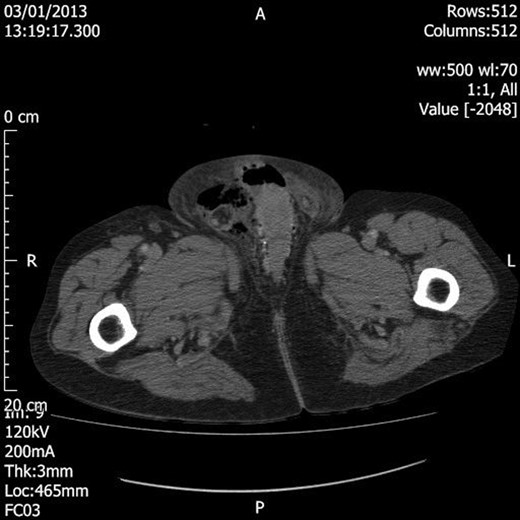

Blood tests showed grossly elevated white cell count and acute kidney injury, along with markedly deranged clotting parameters (Table 1). The patient was resuscitated with further intravenous fluids, and broad-spectrum antibiotics were commenced. Prothrombin complex concentrate was administered to correct the international normalized ratio. En route to theatre for surgical debridement the patient underwent computed tomography (CT) to assess for intra-abdominal sepsis, given the clinical findings of lower abdominal peritonism and the recent reported lower abdominal pain. This revealed a large amount of loculated gas mainly within the right hemiscrotum with superior extension into the inguinal canal, lower anterior abdominal wall and subcutaneous soft tissue, and lateral extension towards the right buttock; along the right lateral pelvic wall, there was a 10 × 4 × 6 cm collection containing fluid and air. No bowel loops were identified extending into the inguinal region (Figs 1 and 2).

Axial section CT image demonstrating loculated air within the right hemiscrotum.

Coronal section CT image demonstrating extension of the loculated air superiorly into the inguinal canal and lower anterior abdominal wall and laterally into the right buttock. There is also a 10 × 4 × 6 cm fluid and air collection in the right pelvis.